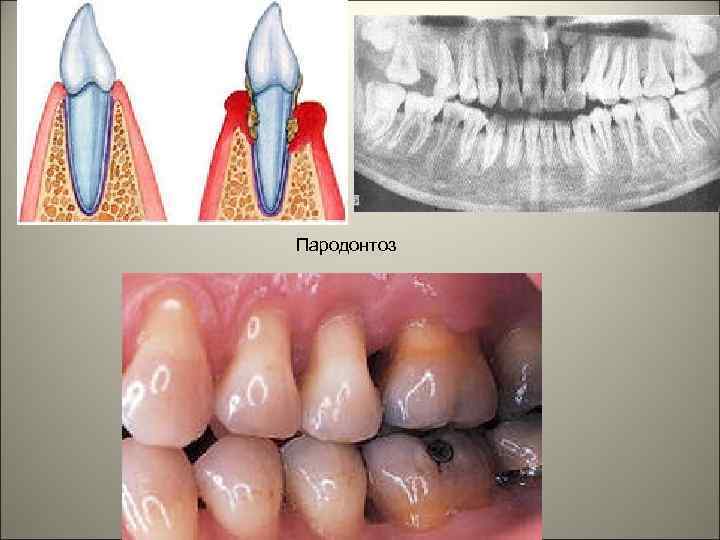

• Пародонтоз – это генерализованное хроническое заболевание, протекающее с рецидивами и ремиссиями, характеризующееся развитием резорбции костной ткани зубной лунки без предшествующего гингивита и пародонтита, в результате чего развивается истончение костных пластинок межальвеолярных перегородок, расширение костномозговых пространств, формирование патологического зубодесневого кармана и выпадение зубов.

Пародонтоз

• Классификация пародонта. 1. По степени тяжести: - легкая – обнажены шейки зубов, но не корни, снижение высоты межзубных перегородок на 1/3; - среднетяжелая – корни зубов обнажены до 1/3, снижение высоты межзубных перегородок до ½. Зубодесневые и пародонтальные карманы отсутствуют. Генерализованная рецессия десны от 3 до 5 мм; - тяжелая – корни зубов обнажены на ½ и более, снижение высоты межзубных перегородок более чем на половину. Генерализованная рецессия десны более 5 мм, подвижность зубов и их выпадение. 2. В зависимости от присоединения воспалительного процесса: неосложненный и осложненный (воспалением).